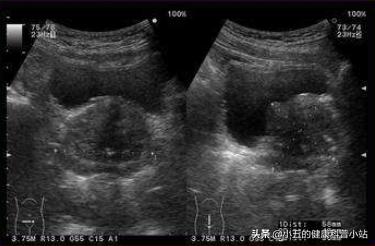

50多岁的张大爷患有慢性前列腺炎多年,平时一直在吃着坦索罗辛控制病情,情况一直还好。最近张大爷开始感觉到小便有点异常,次数明显多,伴有明显的排尿时间延长,有时候甚至要等待1分多钟才能尿出来,而且尿不干净。张大爷不敢大意连忙前来医院进行检查, 通过完善前列腺彩超发现张大爷的前列腺有明显的增生伴钙化,正是这种病情的进展才导致他出现明显排尿障碍 ,看到这个结果, 张大爷也不禁感叹道还是没有躲过去 。

当知道自己确诊为前列腺增生后,张大爷紧张地问道是不是要进行手术 ,医生说目前张大爷的情况还可以用药物控制,但需要在坦索罗辛的基础上加上一种药,加非那雄胺 ,一听要加药张大爷有点不愿意,因为食药三分毒,而且吃了怎么久的坦索罗辛还是避免不了前列腺增生,难道加一种药就行吗? 医生解释道坦索罗辛仅仅可以改善前列腺的症状,但对于前列腺增生还是要依靠非那雄胺才行 。张大爷最后还是接受了医生的建议,通过1个月左右的治疗后,他的临床症状开始明显缓解,服药半年后复查前列腺彩超,发现前列腺的体积也明显缩小。